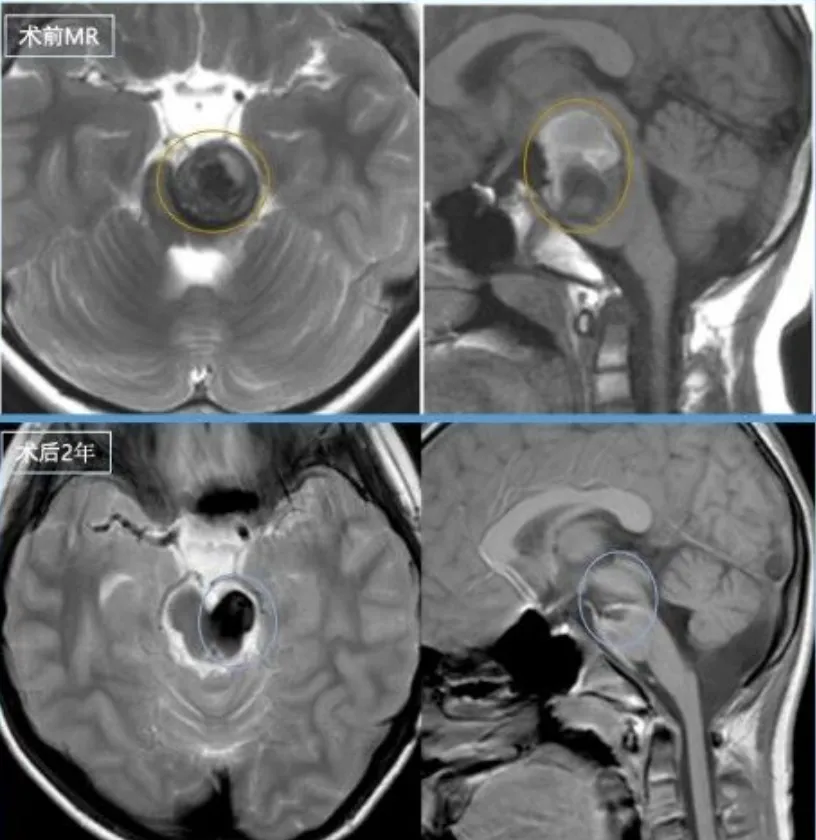

术前情况脑干脑桥偏左侧占位,锥体束受压迫,见含铁血黄素环。

手术日很快来临,巴教授采用了半坐位手术,在术中电生理监测等设备的辅助下,为阳阳顺利全切了病变。

最令阳阳父母泪目的是,孩子的面瘫逐渐缓解,言语清晰如常,甚至能小跑着追球。曾经的“可能瘫痪”“可能失语”被一句句“妈妈看我!”击得粉碎。术后三年复查无复发,他依旧是能量满满的小勇士。